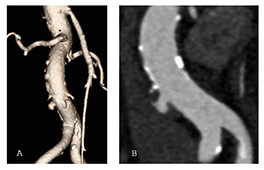

Penetrierendes Aortenulkus in einer 3D-Rekonstruktion (A) und einer zweidimensionalen Computertomographie (B) der infrarenalen Hauptschlagader.

Endovaskuläre Therapie infrarenaler penetrierender Aortenulzera: Ergebnisse einer internationalen Multicenter-Studie

In einer internationalen Multicenter-Studie wurden 260 Patientinnen und Patienten aus zwölf europäischen Gefässzentren analysiert, die zwischen 2018 und 2022 behandelt wurden. Die Mehrheit erhielt eine endovaskuläre Therapie. Die technische Erfolgsrate lag bei über 99 %, die 30-Tage-Mortalität bei 1,5 %. Komplikationen traten vor allem bei symptomatischen oder notfallmässig behandelten PAU auf. Die Ergebnisse bestätigen die endovaskuläre Therapie als sichere und effektive Standardbehandlung infrarenaler penetrierender Aortenulzera.